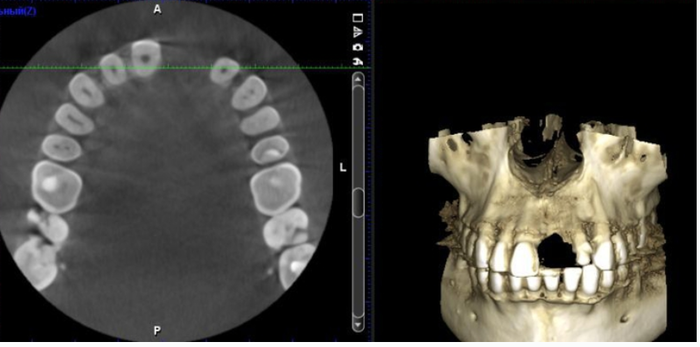

После операции осмотры хирургом проходят по такой схеме: на следующее утро, через неделю, месяц и три месяца. В течении месяца капаются прописанные капли. У меня это были антибиотики, кортекостероиды и натуральная слеза. Это стандартный набор. На осмотре через три месяца помимо проверки остроты зрения мне сделали КТ глаза, чтобы посмотреть, как окончательно улеглись линзы вокруг глазных сосудов.